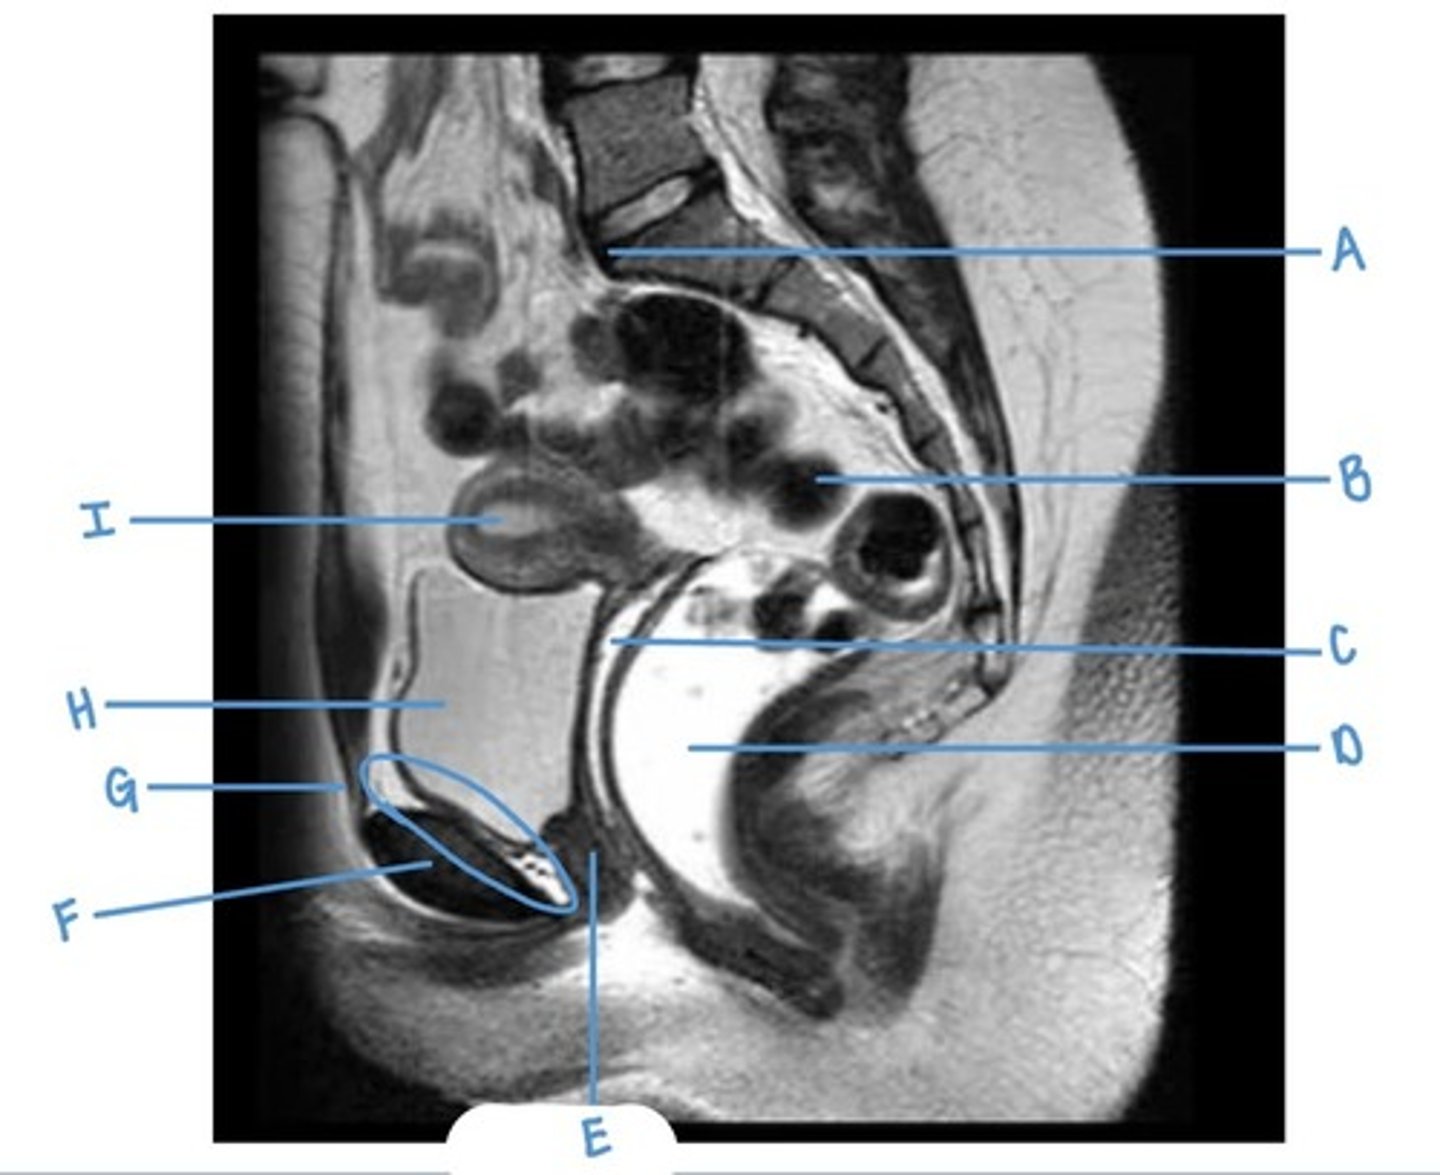

sacral promontory

A

sigmoid colon

B

vagina

C

rectum

D

urethra

E

pubic symphysis

F

retro-pubic space

G

bladder

H

uterus

I